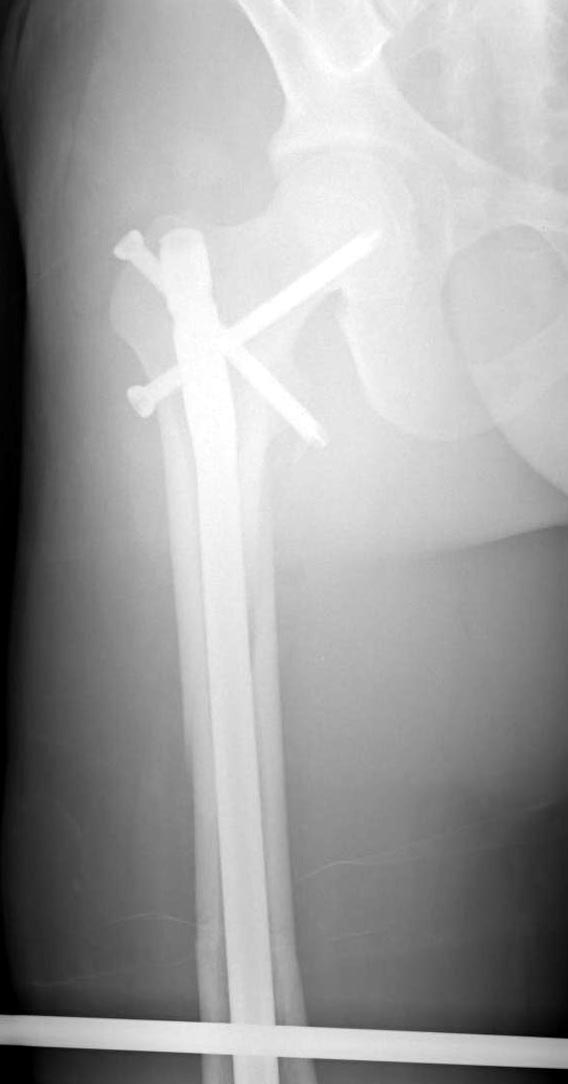

Здесь слайды случая больного с политравмой, включающей сегментарный перелом бедра и повреждение таза с нарушением тазового кольца, разрыв симфиза и перелома крестца зон 2 и 3.

На множественных слайдах важные моменты операции. Хотел бы подчеркнуть, как важно иметь возможности всех необходимых ренгенограмм, включая компютерную томографию и стандартных внутритазовых рентгенограмм (инлет и оутлет).